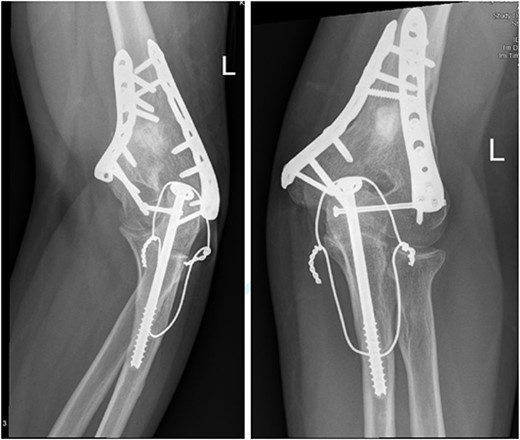

After surgery, the patient was taken back to the ICU and was followed daily by the upper limb orthopedic surgery team for wound care and change of dressings. Four days later, the patient’s condition had improved and he was assessed for distal neurovascular function, which was intact. Afterwards, range of motion was assessed, and no complications were reported before discharge. The patient was kept as an inpatient for almost two more months under the orthopedic trauma team for continuation of management and patient optimization. After discharge, the patient was followed in the orthopedics upper limb and trauma clinic for almost 3 years (Figs 4– 6).

(A). Late follow-up anteroposterior (AP) view of the left elbow after ORIF. (B) Late follow-up lateral view of the left elbow after ORIF.

Our patient was followed afterwards for three years with serial x-rays. No signs of growth arrest or deformity due to our surgical intervention were noted. Instead, on follow up, our patient had a functional range of motion. Elbow range of motion was documented to be 30° extension to almost full flexion and intact pronation and supination. The range of shoulder motion was documented as full. Good healing was observed, but there was some hardware prominence that slightly affected the range of motion, and the patient will be booked for hardware removal. The patient was happy and satisfied about the overall outcome and restored functionality.